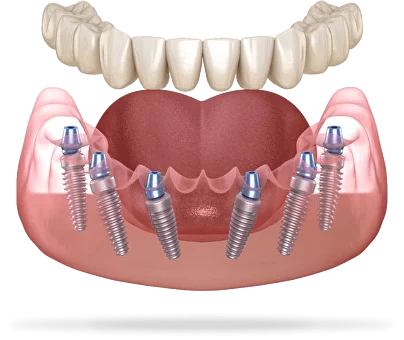

Швейцарская имплантация All‑on‑4 и All‑on -6 являются основным профилем наших врачей по которому они работают ежедневно

«Все на 4-х» на системе Nobel Biocare

от 110 000 рублей

«Все на 6-ти» на системе Nobel Biocare

от 170 000 рублей

- Возможность установки при средней и ярко выраженной убыли кости, а также при заболеваниях пародонта

- Более надёжная фиксация и распределение нагрузки

- Естественный внешний вид, удобство и комфорт

- Подходит при атрофии кости

- Самое быстрое решение при множественном и полном отсутствии зубов и атрофии кости — все зубы за 8 часов.

- Протез надёжно держится во рту, не вызывает рвотного рефлекса

- Улучшение дикции, омоложение контура лица

- Минимум противопоказаний, не требует наращивания костной ткани